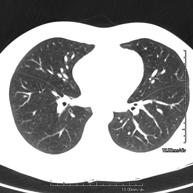

- Chest CT

Diagnostic test that provides high definition anatomical images of the chest (lungs, heart, mediastinum, great vessels, rib cage, etc.) using CT (Computed Tomography) equipment. These images are then examined on a workstation that allows bidimensional reconstructions in different planes of space and also 3D reconstructions (volumetric). Some studies require the use of an iodinated contrast agent to improve image definition.

- High resolution Chest CT

Diagnostic test to examine the lung using CT (Computed Tomography) equipment to obtain two- and three-dimensional images, that allow a highly specific anatomical examination of the lung, being able to assess very small anatomical structures. This technique is very important among patients with suspected lung disease.